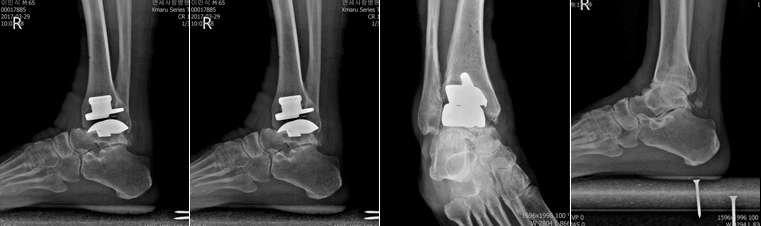

- 수술적 요법 : 관절내시경, 발목고정술, 인공족관절 치환술 등

인공 발목관절의 장점

- 수술 후 한 달 이내에 조기 체중부하 가능

- 계단 등의 보행이 자연스럽고 주변 관절의 퇴행성 변화를 방지

- 신한 관절염 환자들도 정상적인 관절 움직임이 가능

- 재수술은 매우 드물며, 하더라도 최초의 수술보다 시간도 짧고 회복도 빠름